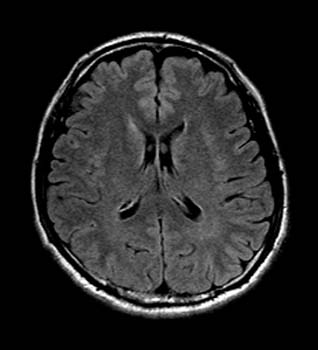

高血圧の末、眼底出血を起こしたのが5年前でした。 先週そのときの悪夢がまた現実に、、視野の狭窄は数時間で消えたので、小さな血管の出血だったのでしょう。 この分で行くと、ボクの頭の血管もときどき小さなものが切れては、密かに吸収されて事なきを得ているってことのようです。

脳ドックというシステムは、15分程度磁場の中に寝ているだけで完了します。2週間後、このような写真が入ったCDが送られてきて、楽しむことが出来ます(^o^)